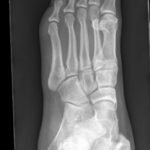

X-rays of the foot were obtained and no radiopaque foreign body was visualized. Due to high clinical suspicion for retained foreign body, a point-of-care ultrasound was performed by applying a high-frequency linear probe at the area of discomfort. In the long axis an ovoid focus of hypoechogenicity (orange outline) is visualized. Within this finding there is a linear focus (yellow line) of increased echogenicity measuring 1 mm in diameter and 1 cm in length. On short axis view, a rectangle focus (green dot) demonstrating shadowing (blue highlight) is seen.

Whenever a patient has a traumatic injury that violates the integrity of the body, there is the possibility of a retained foreign body. It has been reported that missed foreign bodies are the second leading cause of lawsuits in emergency medicine.1 Despite the known risk of litigation, greater than one third of foreign bodies are missed initially on examination.2 This has frequently been attributed to a lack of imaging in conjunction with examination.3 X-rays are thought to be the most common imaging to screen for foreign bodies in extremity trauma.4 Unfortunately, many foreign bodies are not radiopaque on X-ray. Radiopaque foreign bodies are usually more dense than soft tissues and similar to bone density (e.g., metal, stone, or certain types of glass).5 Less dense foreign bodies are radiolucent and not seen on X-ray.